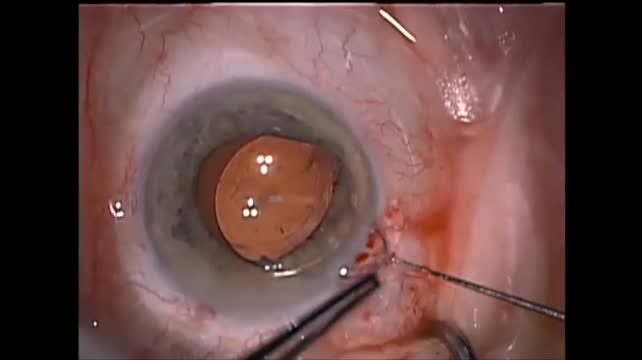

Morgagnian Cataract

Jocelyn S. Kasanardjo, MD, and Gelre Ziekenhuizen Apeldoorn, MD